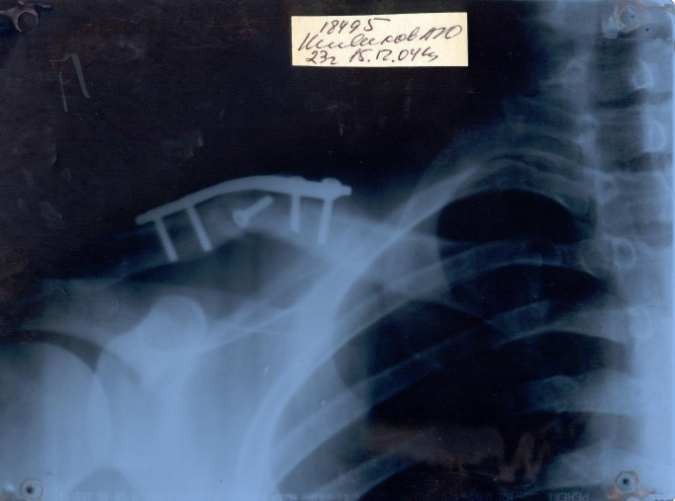

а ВОТ И МОЯ РУКА . СЛОМАЛ В АВГУСТЕ НЕ СРОСТАЕТСЯ ТАК ДО СИХ ПОР И КАТАЮСЬ.

Нажмите на изображение для увеличения

Название: gudron_911.jpg

Просмотров: 2624

Размер:	36.8 Кб

ID:	6041